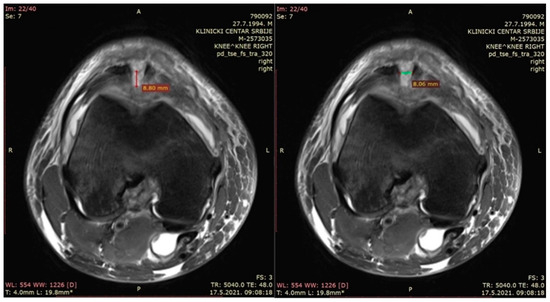

- The depth of the patellar bone defect (mm)—a variable used to assess the depth of the bone defect from the first section caudal to the top of the defect in a transverse plane in the t2_tse_sag sequence at the center of the defect, as defined using the sagittal plane (Figure 3—left).

- The width of the patellar bone defect (mm)—a variable used to assess the width of the bone defect from the first section caudal to the top of the defect in a transverse plane in the pd_tse_fs_tra sequence (Figure 3—right).